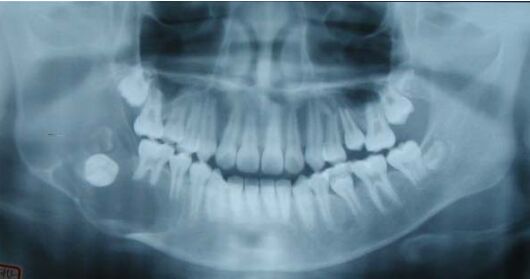

43.一位 12 歲青少年,無意間發現右臉頰無痛腫脹的情形,經環口放射線影像檢查 (panorex),於右側下顎骨呈現一處多室性病灶(如下圖所示)。有關此例之診斷推論,下列那一項最不合理? (A) 若其右側下齒槽神經支配區域有麻木現象,可以合理懷疑為造釉細胞瘤(ameloblastoma) (B) 以針頭抽吸(needle aspiration)呈現淡黃色清澈液體,可以懷疑為含齒性囊腫(dentigerous cyst) (C)以針頭抽吸(needle aspiration),初期呈淡黃色清澈液體,繼而呈現淡紅色液體,則應可 懷疑是 aneurysmal bone cyst (D) 由其右側下顎第一大臼齒牙根型態來看,有明顯病理性吸收之現象